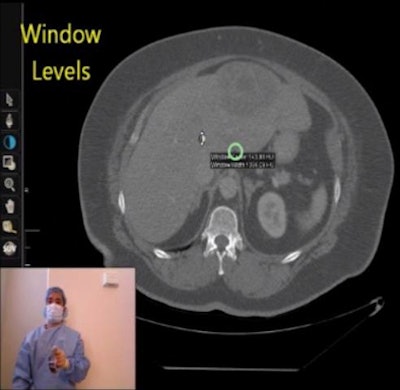

![]() |

| Screenshot demonstrates the Apple iPad for intraoperative imaging review using finger touches and swipes. In this case, the user is employing the zoom function to enhance visualization of the liver lesion. A limited toolbar is at the bottom of the display. |